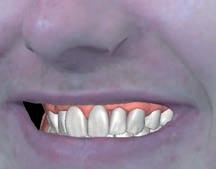

Visualise before you provisionalise

At this early stage of diagnostic work-up, prior to any operative intervention, the clinician and the technician can now communicate to each other and, most importantly, to the patient, in an understandable visual rhetoric, a precise end goal of treatment from which a meeting of the minds may be achieved (Figures 6 and 7).5

Conclusions

Given the serious, irreversible and biologically expensive nature of prosthodontic treatment modalities, a precise end outcome of treatment should be visualised in a language that all stakeholders can understand prior to undertaking significant changes to a dentition. Complete digital workflows that allow the combination of dentofacial 3D data are emerging as an indispensable contemporary tool for restorative clinicians.16

FIGURE 6: Prior to any irreversible and biologically expensive operative intervention, the tripartite stakeholders (patient, clinician and dental technician) of the reconstruction can achieve a precise meeting of the minds in a universally understandable visual rhetoric regarding the intended end goal of treatment.

FIGURE 7: Close-up extra-oral and intra-oral views illustrating satisfying contours of a proposed definitive restoration.